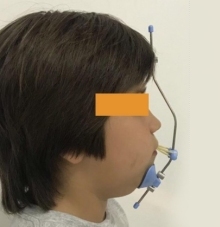

Corregir oportunamente las discrepancias esqueléticas, e intentar mejorar la armonia de los maxilares mejorando significativamente el aspecto facial, utilizando para esto una amplia variedad de aparatos removibles y fijos, tanto en niños como jóvenes en etapa de crecimiento.